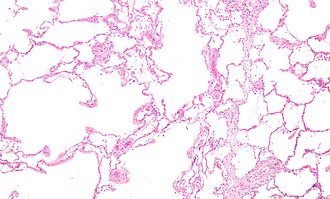

Emphysematous changes. H&E stain. | |

| LM | alveoli too large, thin septa (no interstitial thickening) |

Microscopic

Features:[5]

- Large alveoli.

- Thin septa (no interstitial thickening).